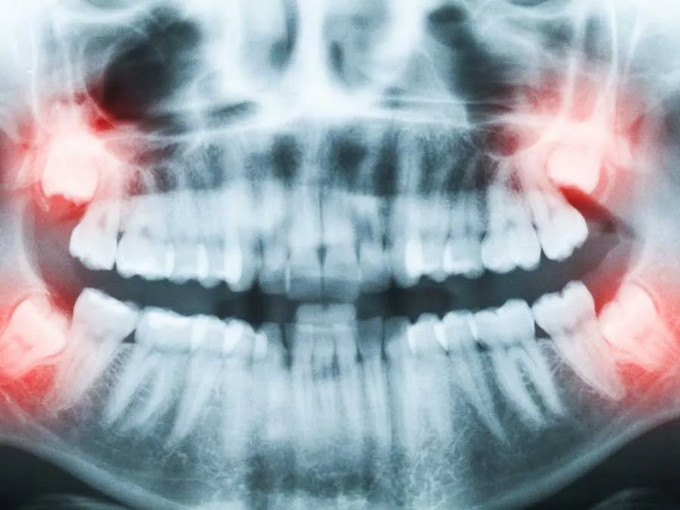

智齒通常在18~25歲萌出。因?yàn)轭M骨空間不足、牙胚位置異常或角度不正,智齒長(zhǎng)不出來,斜著或橫著長(zhǎng),被牙齦或骨頭部分或完全覆蓋,就稱為埋伏(阻生)智齒。這類智齒與口腔之間常形成難以清潔的“盲袋”,為細(xì)菌聚集提供條件。

4. 形成囊腫或出現(xiàn)占位:影像可見病灶擴(kuò)大、骨質(zhì)被吸收。

影像學(xué):口腔CT(CBCT)通常是必要的,可以了解埋伏牙的位置與角度,評(píng)估根形、與下牙槽神經(jīng)和上頜竇的關(guān)系。